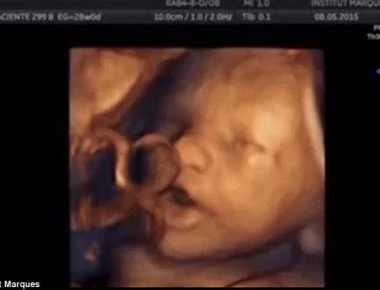

Κι όμως...Τα έμβρυα «τραγουδούν» από την 16η εβδομάδα κύησης (βίντεο)

Ερευνα αποδεικνύει ότι τα έμβρυα, αντιδρούν σε ηχητικά ερεθίσματα και «τραγουδούν». Για πρώτη φορά ερευνητές του Ινστιτούτου Marques στην Βαρκελώνη έδειξαν ότι το έμβρυο μπορεί να ανιχνεύει ήχους και ...